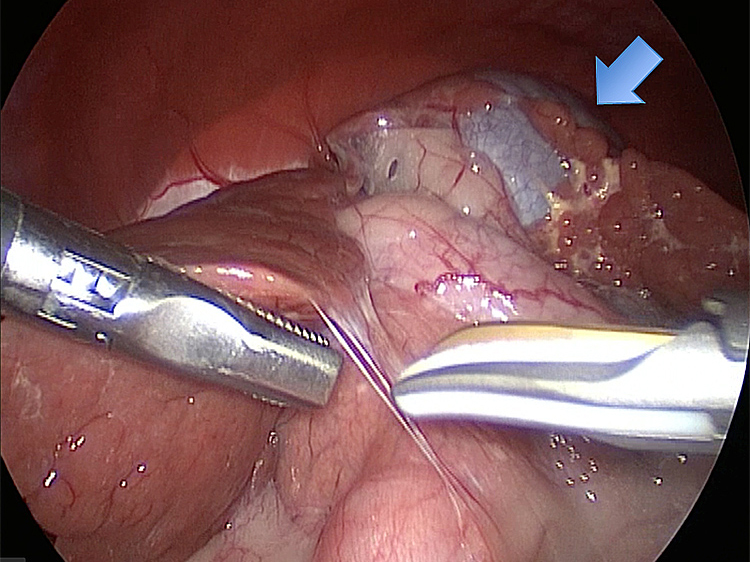

他院より紹介。胆嚢炎がひどく繰り返す嘔吐がありました。 腹膜と一部横隔膜に胆嚢ががっちりと癒着していました。 体重が2kgと体も小さかったのですが、飼い主さんの希望もあり、腹腔鏡下で手術を実施することになりました。

丁寧に丁寧に出血をコントロールしながら少しずつ手術をすすめていきます。

癒着(矢印)がひどく胆嚢を確認することができませんでした。 このように癒着しているときはギリギリで剥がすとひどく出血をおこすことがあるので無理にはがそうとしないで、脂肪の血管に注意しながら脂肪ごと剥がしていきます。

胆嚢(矢印)の取り囲むように肝臓や腸が癒着していました。肝臓の表面はボコボコしています。